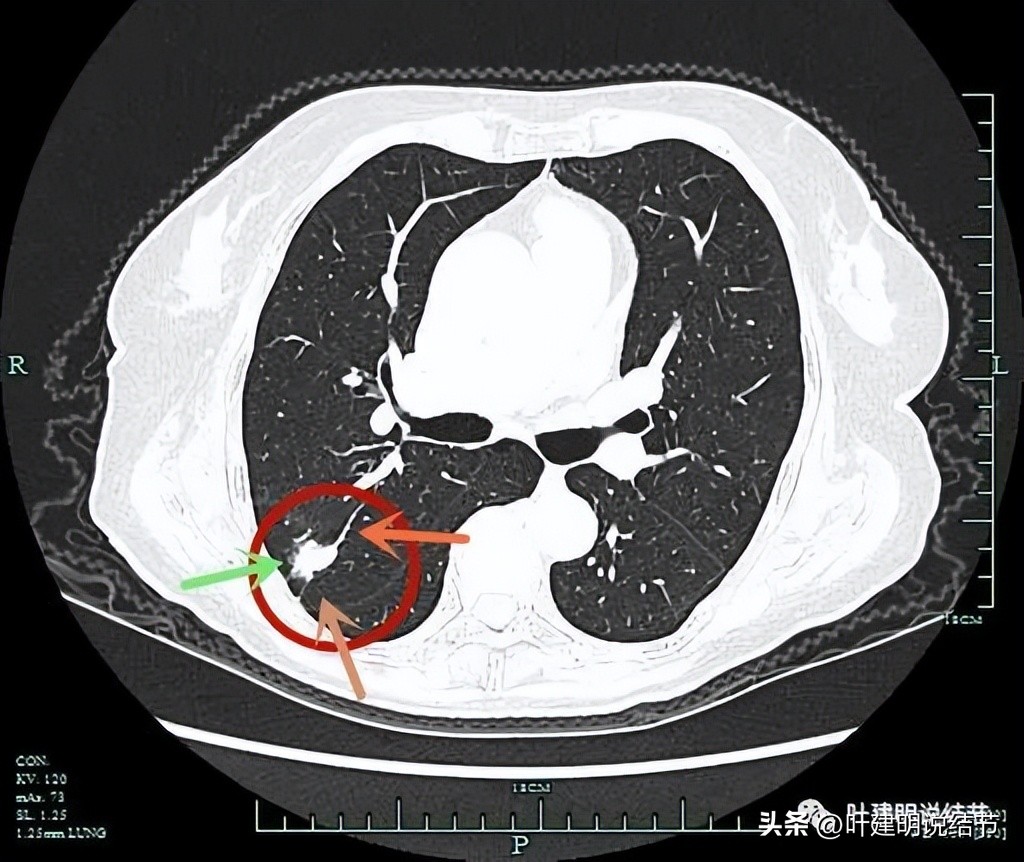

病灶有分叶(砖色箭头);边缘区有磨玻璃成分(绿色箭头);血管进入并异常增粗(桔色箭头)。

病灶磨玻璃成分(绿色箭头);紫色箭头所指处边缘较平,没有明显毛刺征;血管进入是异常增粗的(桔色箭头)。

边缘区略显模糊。